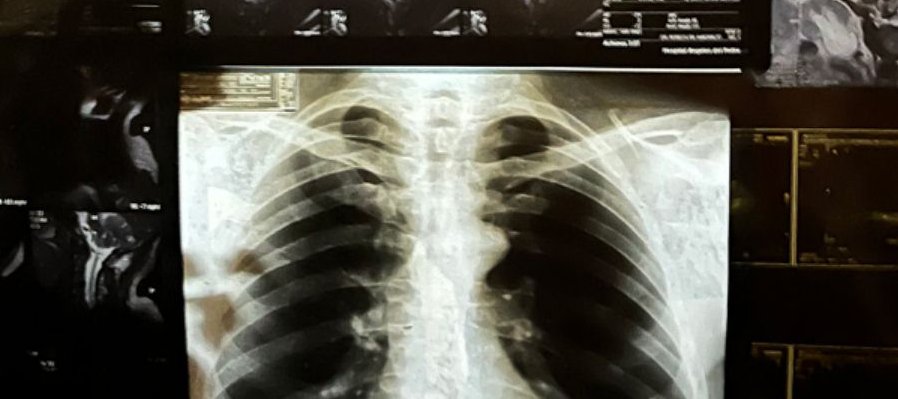

Una radiografía puede revelar la trayectoria vital del cuerpo, la historia vivida y lo que aún le aguarda. Tras una experiencia personal, Héctor de Anda (Jalisco, 1950) recurre a este material para elaborar sobre su relación con la enfermedad y el deterioro del cuerpo. Destinadas a un uso privado y a conservarse en un expediente médico, el artista las reutiliza para componer un dibujo configurado por recortes corporales (huesos, tejidos) que flotan en el vacío. No están agrupados según el donante o bajo ningún otro orden lógico: lo único que los une es que son fragmentos internos de origen humano.

En “Autoradiográficas”, el artista presenta una intervención a la estructura del museo para configurar un dibujo-vitral de nuestro propio interior. Hay un dolor latente en este collage intuitivo y visceral. Esta obra toma como punto de partida la frialdad y objetividad de la imaginería de las ciencias, haciéndolas retornar como huellas de marcas y heridas personales. Se vuelcan angustias y miedos; pero, sobre todo, esta pieza nos confronta con la inminencia del desgaste humano, recordándonos que estamos siempre expuestos a desgarrarnos, rompernos y enfermarnos.